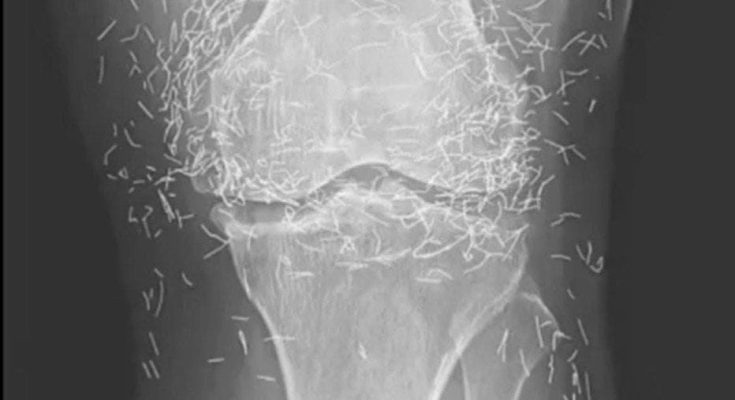

Years later, when doctors took X-rays to evaluate her knee condition, they weren’t prepared for what appeared on the images. Her knees were filled with dozens of bright, metallic flecks — tiny needles embedded deep within the joint area.

The findings were later documented in a case published by the New England Journal of Medicine.

Beyond inflammation, the needles created another problem: imaging complications. Metal objects can obscure parts of the anatomy on X-rays, making it harder for doctors to clearly assess joint damage or disease progression.

Even more concerning, the presence of metal inside the body can make certain scans dangerous. MRI machines rely on powerful magnetic fields, and embedded needles may shift during scanning, potentially damaging blood vessels or surrounding tissue. In short, future diagnostic options for this patient became limited.